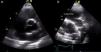

ETE: inserção das válvulas aurículo ventriculares no mesmo plano (seta), de acordo com associação de TCCGV com defeito de canal AV, que ocorre em até 75% dos casos2 (vídeo 3).

ETE: aurícula recebendo duas veias cava (aurícula direita); válvula AV morfologicamente mitral em posição direita; eletrocateter (seta branca) identificando veia cava superior e ventrículo morfologicamente esquerdo em posição direita; SIA com shunt residual baixo (seta azul) (vídeos 4 e 5).

| Inserção da válvula AV morfologicamente tricúspide em posição esquerda num plano inferior ou no mesmo plano do que a válvula AV em posição direita (Figura 4) |

| Ventrículo morfologicamente esquerdo (sem infundíbulo), relacionado com aurícula recetora de duas veias cava. Neste caso, observa‐se trajeto de eletrocateter identificado em ambas as cavidades (Figura 5) |